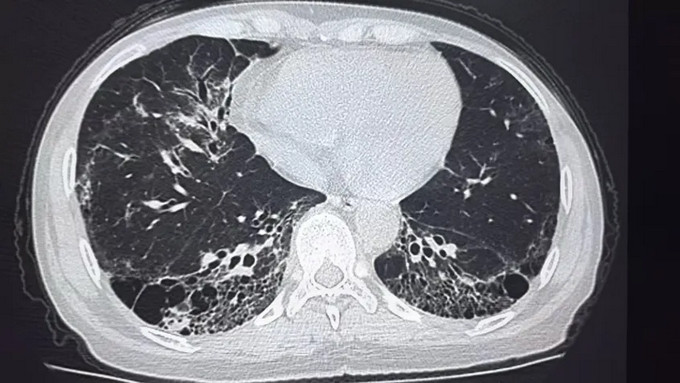

呼吸科:通过高分辨率CT(HRCT)观察肺部纤维化或炎症痕迹,判断病变范围;

影像科:像“肺部侦探”,通过CT图像细微差别区分炎症、纤维化或血管问题;

擅长:特发性肺纤维化、结缔组织病相关肺间质病变的肺病高分辨率CT特征解析与鉴别诊断;熟练应用人工智能辅助影像分析,提升早期肺纤维化检出率及预后预测精度。